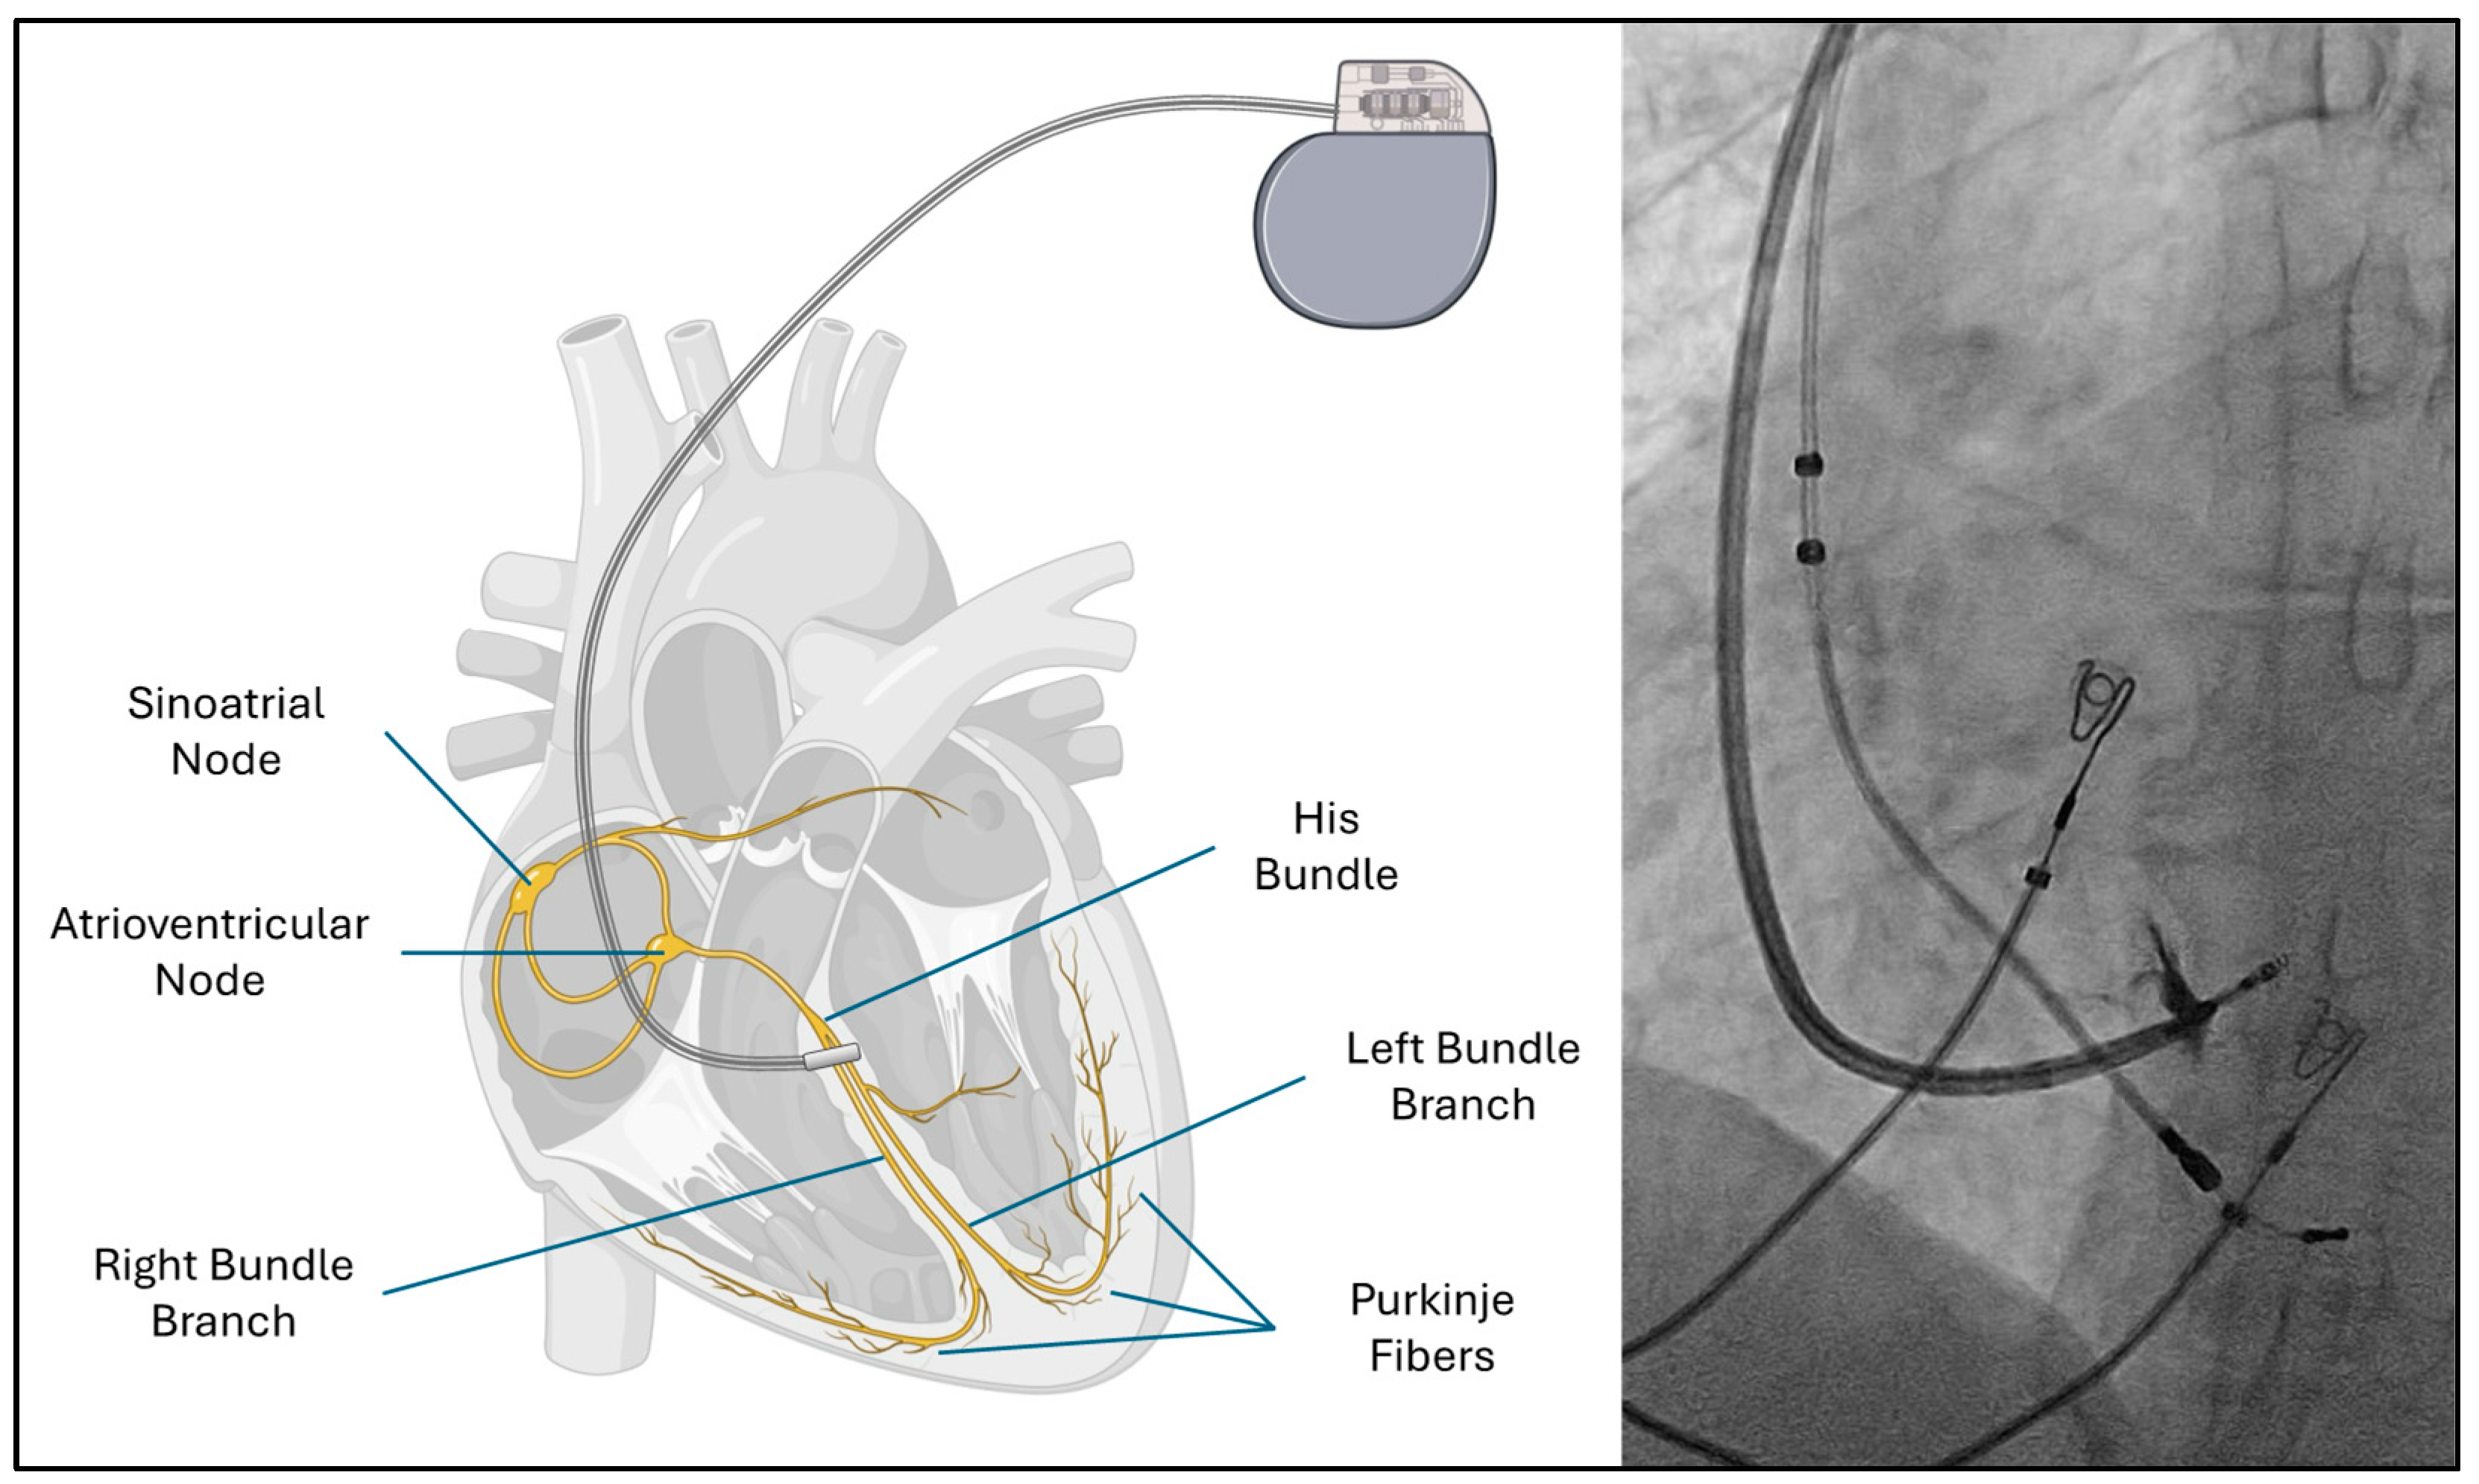

- Schmitt, J.; Althoff, T.; Busch, S.; Chun, K.R.J.; Dahme, T.; Ebert, M.; Estner, H.; Gunawardene, M.; Heeger, C.; Iden, L.; et al. Left bundle branch (area) pacing“: Sondenpositionierung und Erfolgskriterien—Schritt für Schritt [Left bundle branch (area) pacing: Lead positioning and implant criteria-step for step]. Herzschrittmacherther Elektrophysiol. 2024, 36, 82–90. [Google Scholar] [CrossRef]